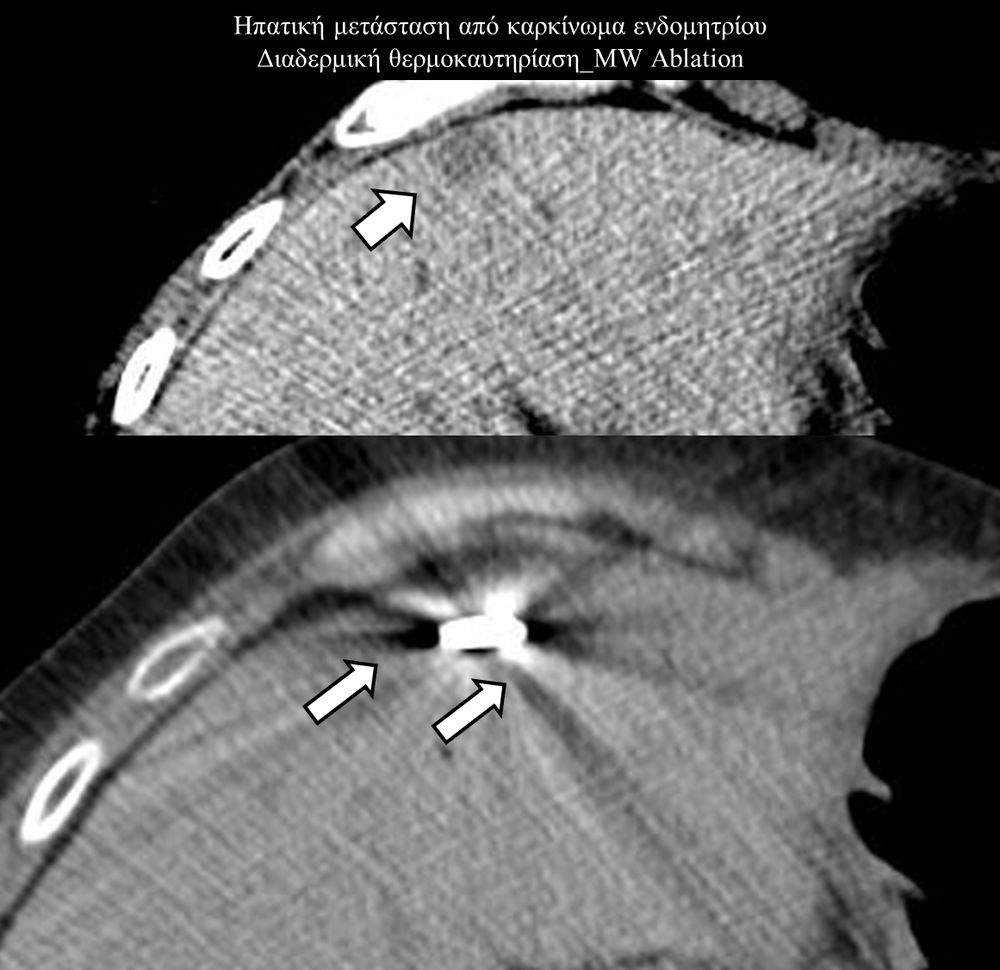

Πρόκειται για την πιο σύγχρονη τοπική θεραπεία όγκων του ήπατος, του νεφρού, του πνεύμονα, των οστών και των όγκων μαλακών μορίων. Παθοφυσιολογικά βασίζεται στην τοπική καταστροφή των καρκινικών κυττάρων με τη δημιουργία ιδιαίτερα υψηλών θερμοκρασιών εντός του όγκου. Αυτό επιτυγχάνεται με τοποθέτηση ειδικών ηλεκτροδίων εντός του όγκου υπό ακτινολογική καθοδήγηση (αξονικός τομογράφος ή υπέρηχος). Τα ηλεκτρόδια αυτά παράγουν υψηλή θερμοκρασία είτε με τη βοήθεια ραδιοσυχνοτήτων (RFablation), είτε με τη βοήθεια μικροκυμάτων (MWablation) και προκαλούν πηκτική νέκρωση των καρκινικών κυττάρων χωρίς να επηρεάζουν τα φυσιολογικά κύτταρα.Το αποτέλεσμα είναι μόνιμο.